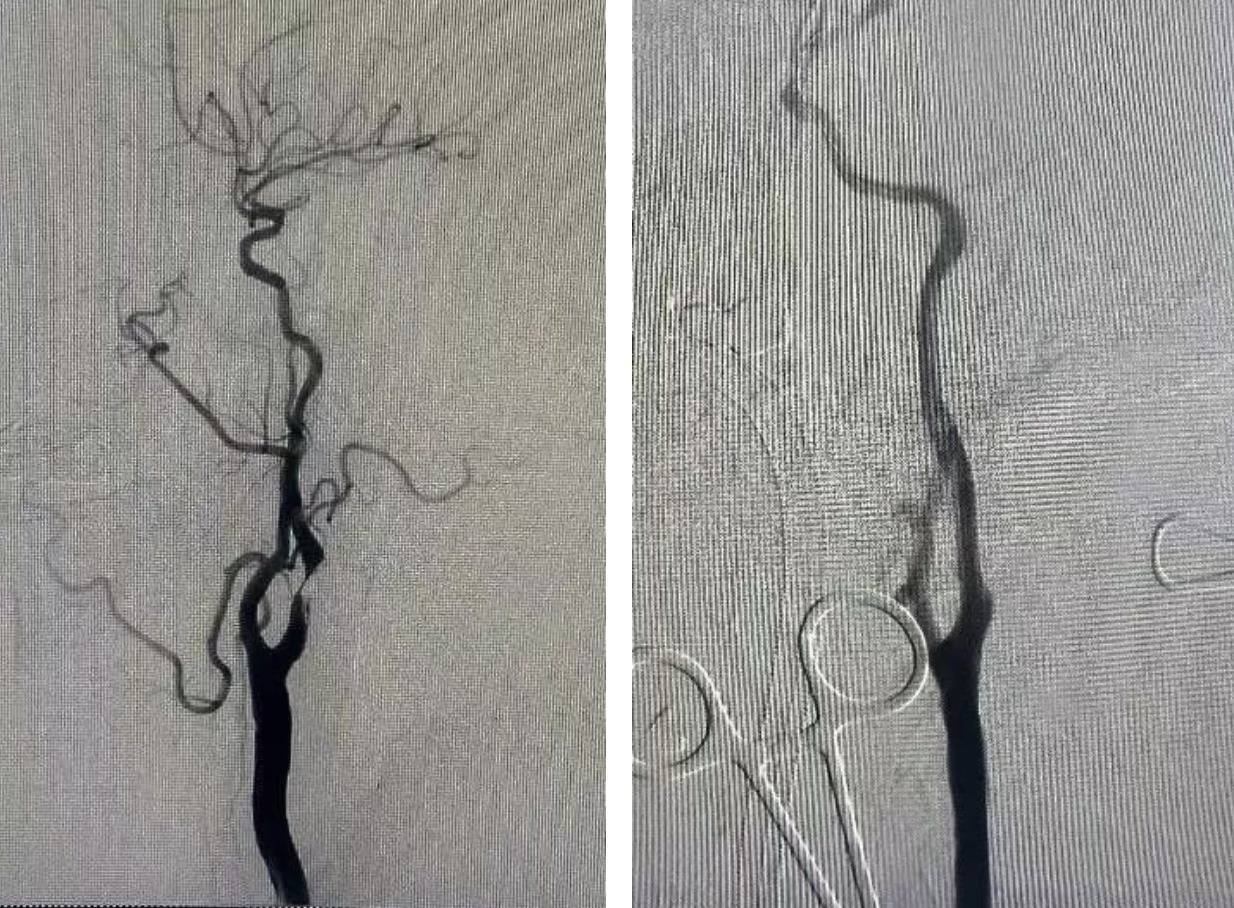

r患者因发作性左手无力来潍坊市中医院东院区脑病重症急救科就诊。患者既往有高血压病、糖尿病病史多年,检查后发现右侧大脑半球分水岭梗死、右侧颈内动脉重度狭窄伴不稳定溃疡斑块、合并多种基础疾病、弓形不佳,常规手术(CEA和T-FCAS)发生栓子逃逸导致颅内栓塞风险相对较高。

r经过多学科全面细致的术前评估和综合考量,在东院区介入导管室、麻醉科、重症医学科等多学科紧密协作下,东院区脑病重症急救科主任邹云涛为患者实施逆向血流保护下经颈动脉血运重建术(TCAR)。

r1. 颈部微创暴露。于锁骨上方做一长约2厘米的微小切口,精准解剖并显露颈总动脉,为后续介入治疗建立一条直接、可靠的通路。

r2. 建立逆流脑保护(ENROUTE系统)。将颈动脉、体外滤网与股静脉回路连接起来,启动血流逆转程序。瞬间,血流方向发生反转,斑块被逆向血流冲刷而出,并经由体外滤网拦截过滤,实现全程脑保护。

r3. 精准介入治疗。在持续稳定的逆流保护下,依次进行球囊扩张与支架植入。狭窄的血管管腔被逐步打开,血流恢复畅通无阻。

r4. 恢复正常血流。撤除逆流保护装置,仔细缝合切口。术后患者病情平稳,未出现任何神经并发症,恢复良好。